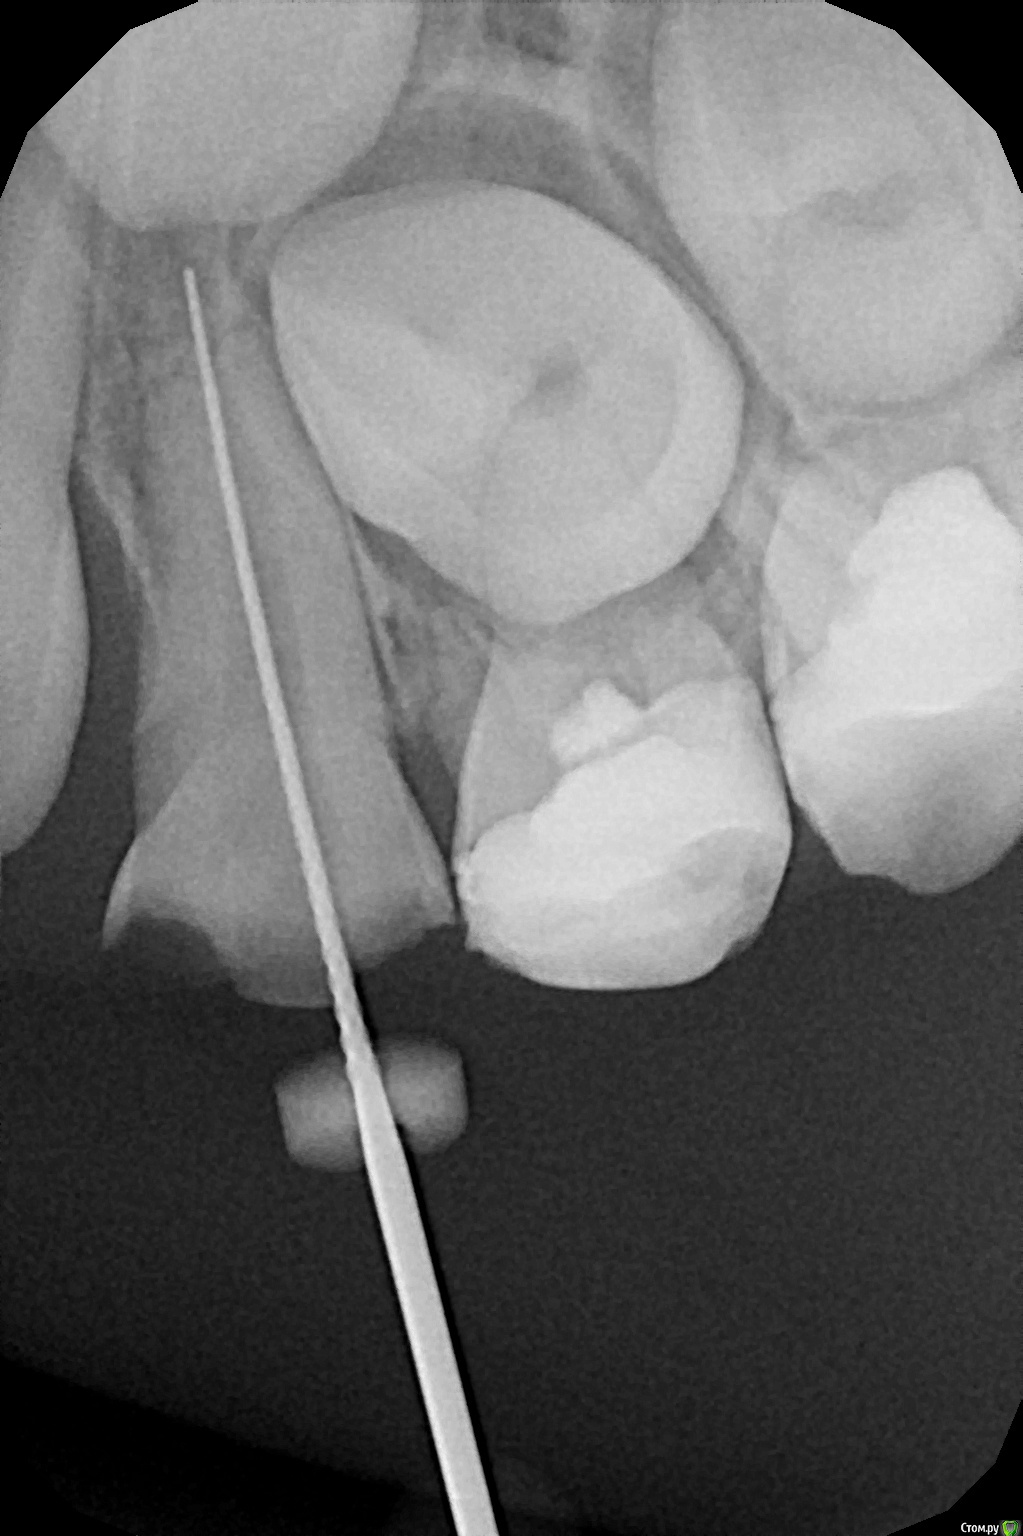

crown Опубликовано 7 июля, 2016 Поделиться Опубликовано 7 июля, 2016 6.4, 7 лет почти, периодонтит. Обработал каналы мотором, вручную лень было, оставил кальций, закрыл временной и как только встала с кресла началась сильная боль, аж до слез, видимо анестезия начала отпускать. Раньше таких проблем не было, обычно все гуд. За апекс не выходил, мед. обработка гипохлорит + перекись. Ссылка на комментарий

CRAZYDUCK Опубликовано 7 июля, 2016 Поделиться Опубликовано 7 июля, 2016 А я перекись не использую для каналов.у детей вообще каналы не мыла ей,а у взрослых промывала периодонтиты -даже под анестезией больно было или неприятные ощущения ,перекись же пениться начинает при контакте с кровью или экссудатом. В этом случае может такая же картина была ? Ссылка на комментарий

Джима Опубликовано 7 июля, 2016 Поделиться Опубликовано 7 июля, 2016 (изменено) Оксан, у меня тоже так бывало, и без перекиси. С чем связать не знаю, помогало только анестезию сделать проводниковую. Сейчас перед пломбировкой заранее нурофен даю, если вспомню. Изменено 7 июля, 2016 пользователем Джима Ссылка на комментарий